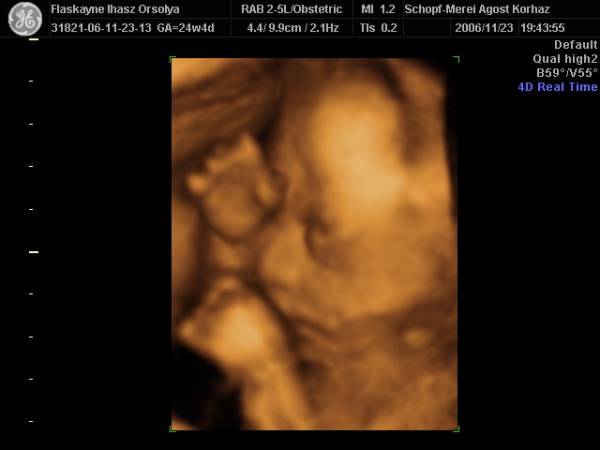

És aznap délután 4D!!!